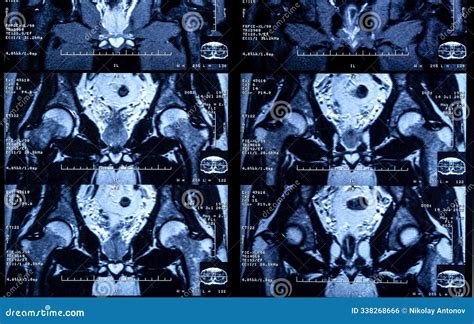

By utilizing magnetic fields and radio waves, the machine generates cross-sectional images that allow radiologists to assess the structural integrity of the knee with extreme precision.

You will lie on a motorized table that slides into the center of the machine. The technician will position your knee within a specialized "coil," which acts like an antenna to capture the images. During the scan, you will hear loud tapping or thumping noises; this is normal and caused by the machine's magnetic coils changing rapidly. You will be provided with earplugs or headphones to make the experience more comfortable.

Once the scan is complete, a radiologist will interpret the images and compile a report. This report will be sent to your primary physician or orthopedist. It is important to note that the findings in your MRI knee joint report must be correlated with your physical symptoms. Sometimes, an MRI might show minor wear and tear, such as mild osteoarthritis, that is common for your age and may not be the primary source of your pain.